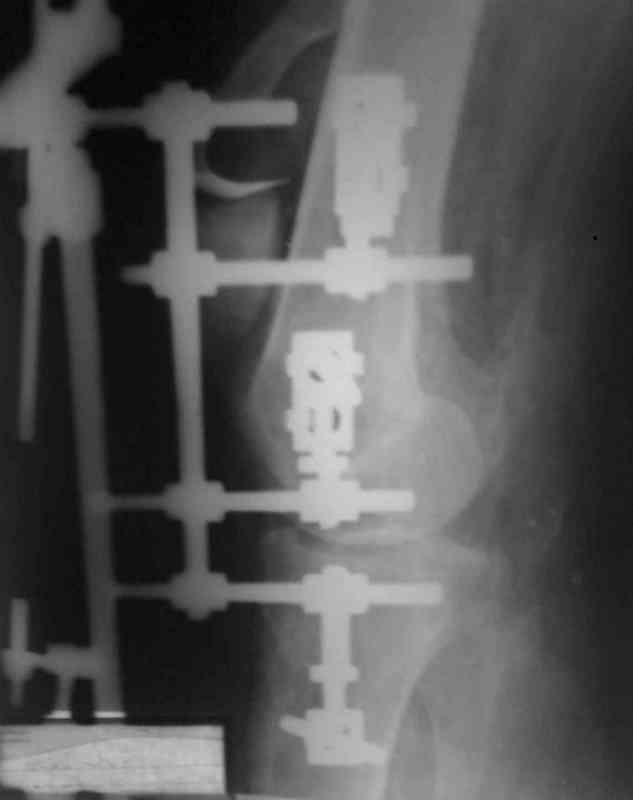

Аппарат внешней фиксации удаляется в 6-7 недель,

предпочтительно под общим обезболиванием, во время

удаления проверяется стабильность и амплитуда движения в коленном суставе с редрессацией.

При пользовании стержневых наружных фиксаторов,

надо придерживаться правила проведения стержней подальше от зоны, на бедре лучше накладывать стержни косо передне-латерально, между брюшками прямой и vastus lateralis, а на голени по передне-медиальной поверхности большеберцовой кости, где отсутствует мышцы, иначе

восстановление движения в суставе тяжелее из-за

прошитых мышц спицами или стержнями аппарата.